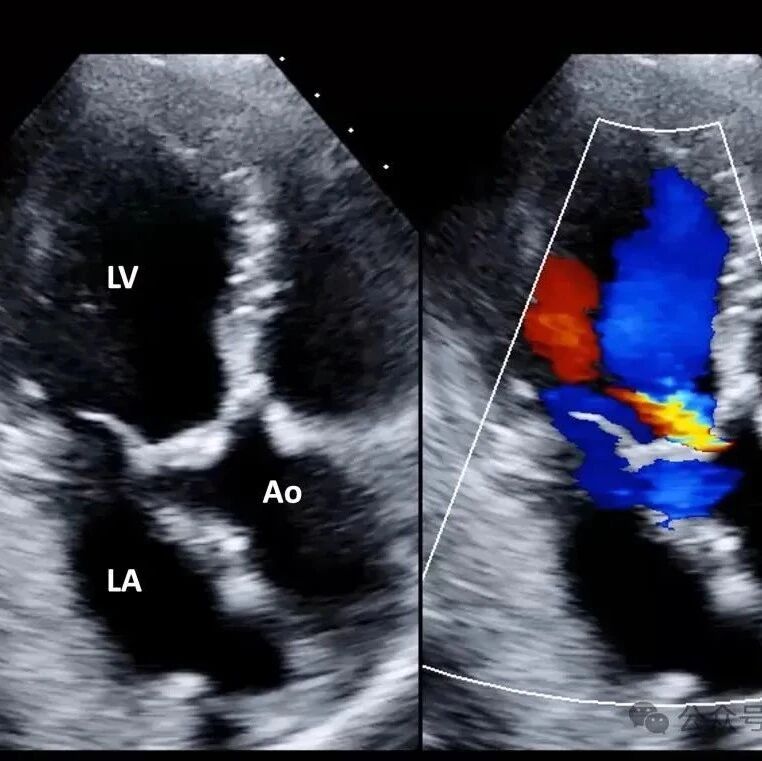

如何使用超声规范评估主动脉瓣狭窄?